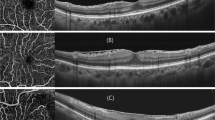

Due to the difficulty in distinguishing ERM from fundus images, the main methods for diagnosing ERM are optical coherence tomography (OCT) and optical coherence tomography angiography (OCTA) [10]. ERM formation is a fibrotic process of myofibroblasts, and exposes the retina to anteroposterior and tangential forces [11]. Additionally, tangential forces drag the retina from its original position, and can be clearly identified when looking at the vascular displacement [12]. Anteroposterior forces cause vertical traction, resulting in leads to a thickening of the macular, which can easily be assessed by OCT [9].

images while taking the color fundus image. The device applies two different wavelengths of light to simultaneously acquire two wavelength-dependent images of the fundus. The content ratio of oxyhemoglobin and deoxyhemoglobin in the blood reflects the degree of SO2 [19]. These two proteins are insensitive to 570-nm light (isoabsorption), and sensitive to 610-nm light (unequal absorption), so the 570- and 610-nm images can reflect the SO2 situation. Color fundus image was used to evaluate the vascular morphology, and the 570-nm and 610-nm images were used to evaluate the blood vessel SO2 level. Figure 2a shows a dual-modal fundus camera, and the acquired images. The resolution of the color fundus image is \(2304\times 1728,\) the resolution of the 570-nm image and 610-nm image is \(1936\times 1456\), the resolution of OT-110 M is \(4.54\mu m\), and the field of view is 45°.